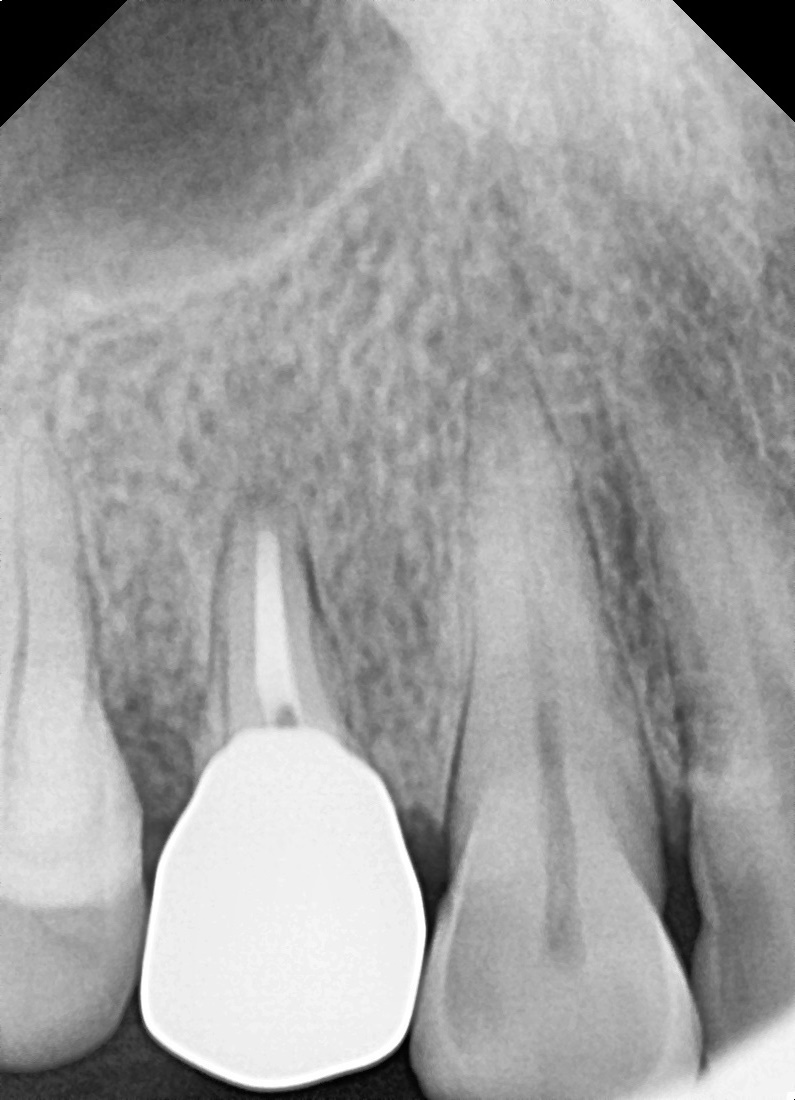

치근단절제술

뿌리 끝까지 염증이 번진 앞니

Before

After

재신경치료 및 치근단절제술 후 병소 완치